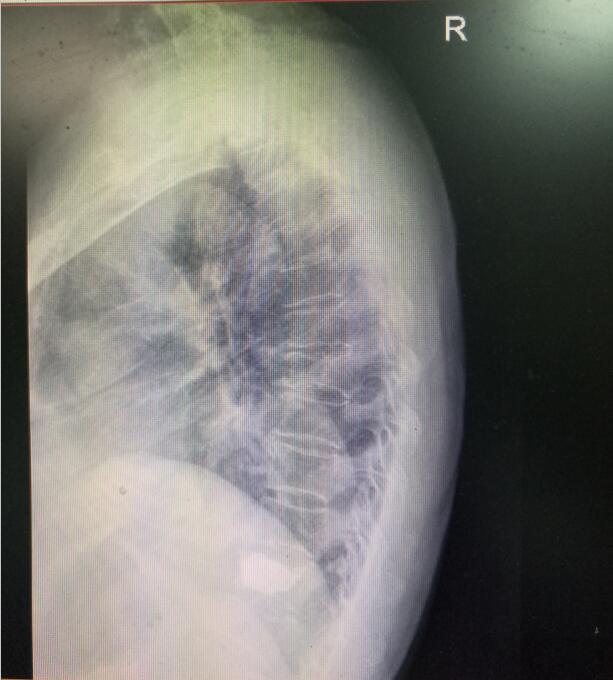

術(shù)后DR(數(shù)字化的x射線)